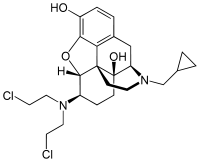

The pharmacodynamic response to an opioid depends upon the receptor to which it binds, its affinity for that receptor, and whether the opioid is an agonist or an antagonist. For example, the supraspinal analgesic properties of the opioid agonist morphine are mediated by activation of the μ1 receptor; respiratory depression and physical dependence by the μ2 receptor; and sedation and spinal analgesia by the κ receptor. Each group of opioid receptors elicits a distinct set of neurological responses, with the receptor subtypes (such as μ1 and μ2 for example) providing even more [measurably] specific responses. Unique to each opioid is its distinct binding affinity to the various classes of opioid receptors (e.g. the μ, κ, and δ opioid receptors are activated at different magnitudes according to the specific receptor binding affinities of the opioid). For example, the opiate alkaloid morphine exhibits high-affinity binding to the μ-opioid receptor, while ketazocine exhibits high affinity to ĸ receptors. It is this combinatorial mechanism that allows for such a wide class of opioids and molecular designs to exist, each with its own unique effect profile. Their individual molecular structure is also responsible for their different duration of action, whereby metabolic breakdown (such as N-dealkylation) is responsible for opioid metabolism.